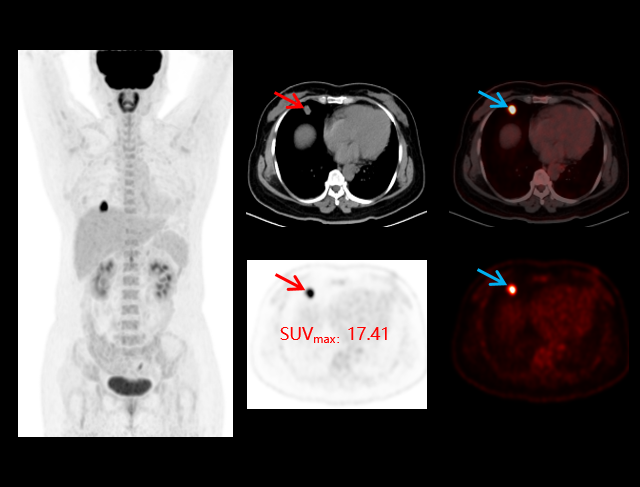

uMI 550搭载自主研发的新一代数字光导探测器,引领PET从「模拟化 」到「数字化 」的时代跨越,系统性能实现多重突破,以超低剂量实现高清成像,大幅提升病灶探测能力;全智能工作流,让临床诊断更精准、更高效、更关爱。

双低剂量,精准影像